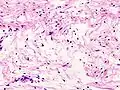

![]() صورة مجهرية من ورم شفاني تظهر كل من منطقة أنتوني الخلوية (وسط ويمين الصورة) وجزئية منطقة B أنتوني فضفاضة (الحافة اليسرى من الصورة)

= 33713 صورة مجهرية من ورم شفاني تظهر كل من منطقة أنتوني الخلوية (وسط ويمين الصورة) وجزئية منطقة B أنتوني فضفاضة (الحافة اليسرى من الصورة)